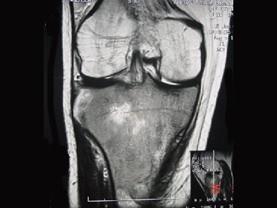

问题 患者女,28岁,右膝跌伤伴疼痛9年,加重及活动障碍1年半,经药物治疗及理疗后病情无好转,既往无特殊病史,查体跛行步态,触痛,请结合所提供的图像,选择最佳选项 ( )

选项 A、软骨肉瘤 B、骨巨细胞瘤 C、滑膜肉瘤 D、骨肉瘤 E、结核

答案 C